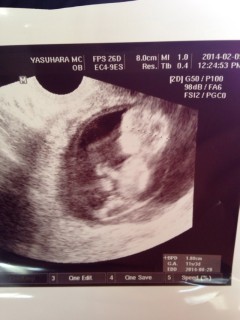

2週間で一気に人間になっていて感動しました!こっち向いてて可愛い♪

仕事が大変で体と心に負担かけてしまっていたので、お腹の赤ちゃんの様子が心配でした。ですが写真の通り。こちらを見て笑っているようで、、感激です!